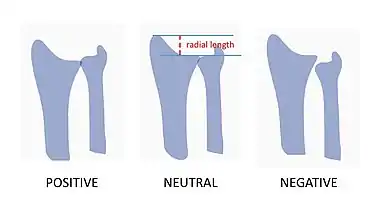

Radial length and ulnar variance

Radial length is an important consideration in distal radius fractures. Radial length should be between 9-12mm.[7] Distal radius fractures typically result in loss of length as the radius collapses from the loading force of the injury. With increasing relative lengthening of the uninjured ulna (positive ulnar variance), ulnar impaction syndrome may occur. Ulnar impaction syndrome is a painful condition of excessive contact and wear between the ulna and the carpus with an associated is a degenerative tear of the TFCC.